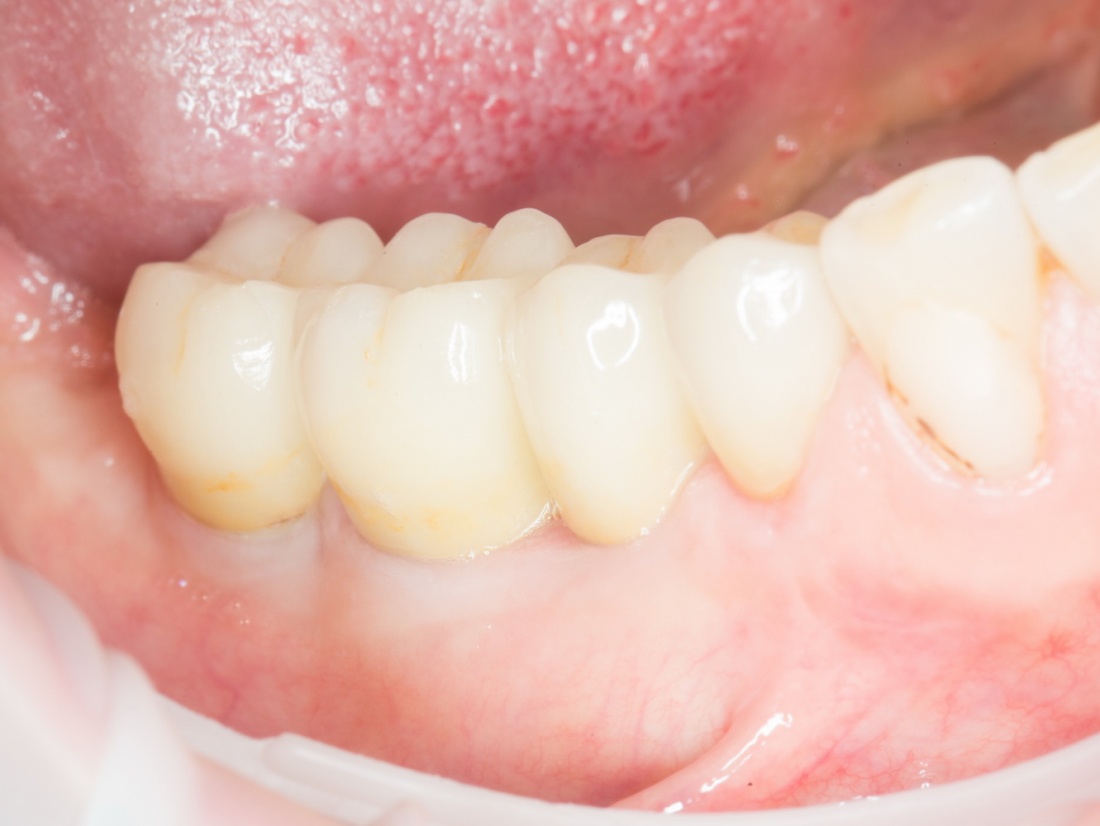

Но это еще не самое веселое. Допустим, мы решили проблему соединения «имплант-абатмент», у нас нет проблем с люфтами, а сам имплантат настолько хорошо интегрировался, что способен любую нагрузку в любом направлении. Возникает другая проблема — размер супраструктуры и соответствие ее нормальной биологической длине коронки зуба:

На фотографии выше, коронки опираются на обычные импланты, но даже в этом случае увеличение высоты супраструктуры усложняет гигиену и требует более пристального дальнейшего наблюдения. С ультракороткими имплантами, если честно, всё еще хуже.